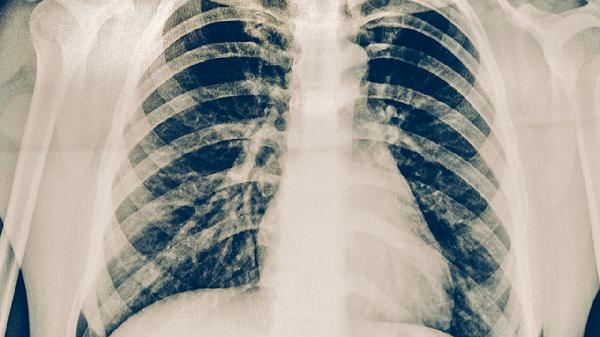

血行播散型肺結(jié)核通常由結(jié)核分枝桿菌通過血液播散至全身引起,常見于免疫力嚴(yán)重低下者。該類型起病急驟,可能出現(xiàn)高熱、寒戰(zhàn)、呼吸困難等癥狀。胸部影像學(xué)檢查可見雙肺彌漫性粟粒樣結(jié)節(jié)。治療需聯(lián)合使用乙胺丁醇片、鏈霉素注射液等藥物,重癥患者需住院治療。